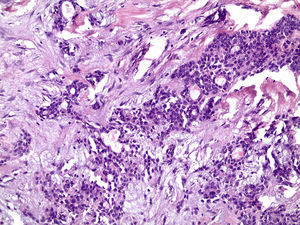

Os cortes histológicos, corados em hematoxilina e eosina, mostraram neoplasia de glândula salivar benigna, constituída por células epiteliais e mioepiteliais, parcialmente envolvida por fina cápsula de tecido conjuntivo fibroso (fig. 5). As células epiteliais encontravam‐se formando lençóis ou estruturas ductiformes, enquanto as células mioepiteliais formavam áreas mixoides, hialinas (fig. 6) ou exibiam aspecto plasmocitoide (fig. 7). O diagnóstico de adenoma pleomórfico foi confirmado. Paciente queixou‐se de desconforto no palato quando se alimentava, durante as 2 primeiras semanas após cirurgia. O paciente está sendo acompanhado clinicamente e, 2 anos após a cirurgia, não apresenta sinais de recidiva da lesão (fig. 8).

Os cortes histológicos mostraram neoplasia benigna de glândula salivar, envolvida por cápsula de tecido conjuntivo fibroso (fig. 14). O parênquima neoplásico é constituído por células epiteliais dispostas em lençóis e estruturas ductiformes, além de células mioepiteliais formando áreas mixoides e hialinas (fig. 15) ou apresentando‐se com morfologia plasmocitoide (fig. 16). O diagnóstico de adenoma pleomórfico foi confirmado. A paciente relatou ausência de dor no pós‐operatório e manteve utilização da placa de acrílico por 4 semanas. A paciente encontra‐se em acompanhamento e o exame clínico após 2 anos da remoção cirúrgica mostrou adequada cicatrização e ausência de sinais de recidiva da lesão (fig. 17).